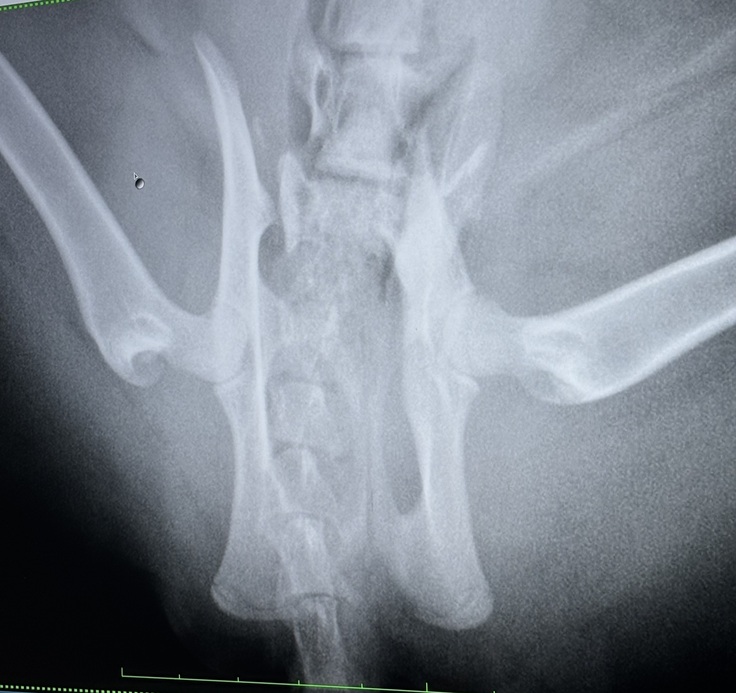

病院に行くと骨盤骨折…

ただ、レントゲンではかなり難しい手術になりそうとのことでした…